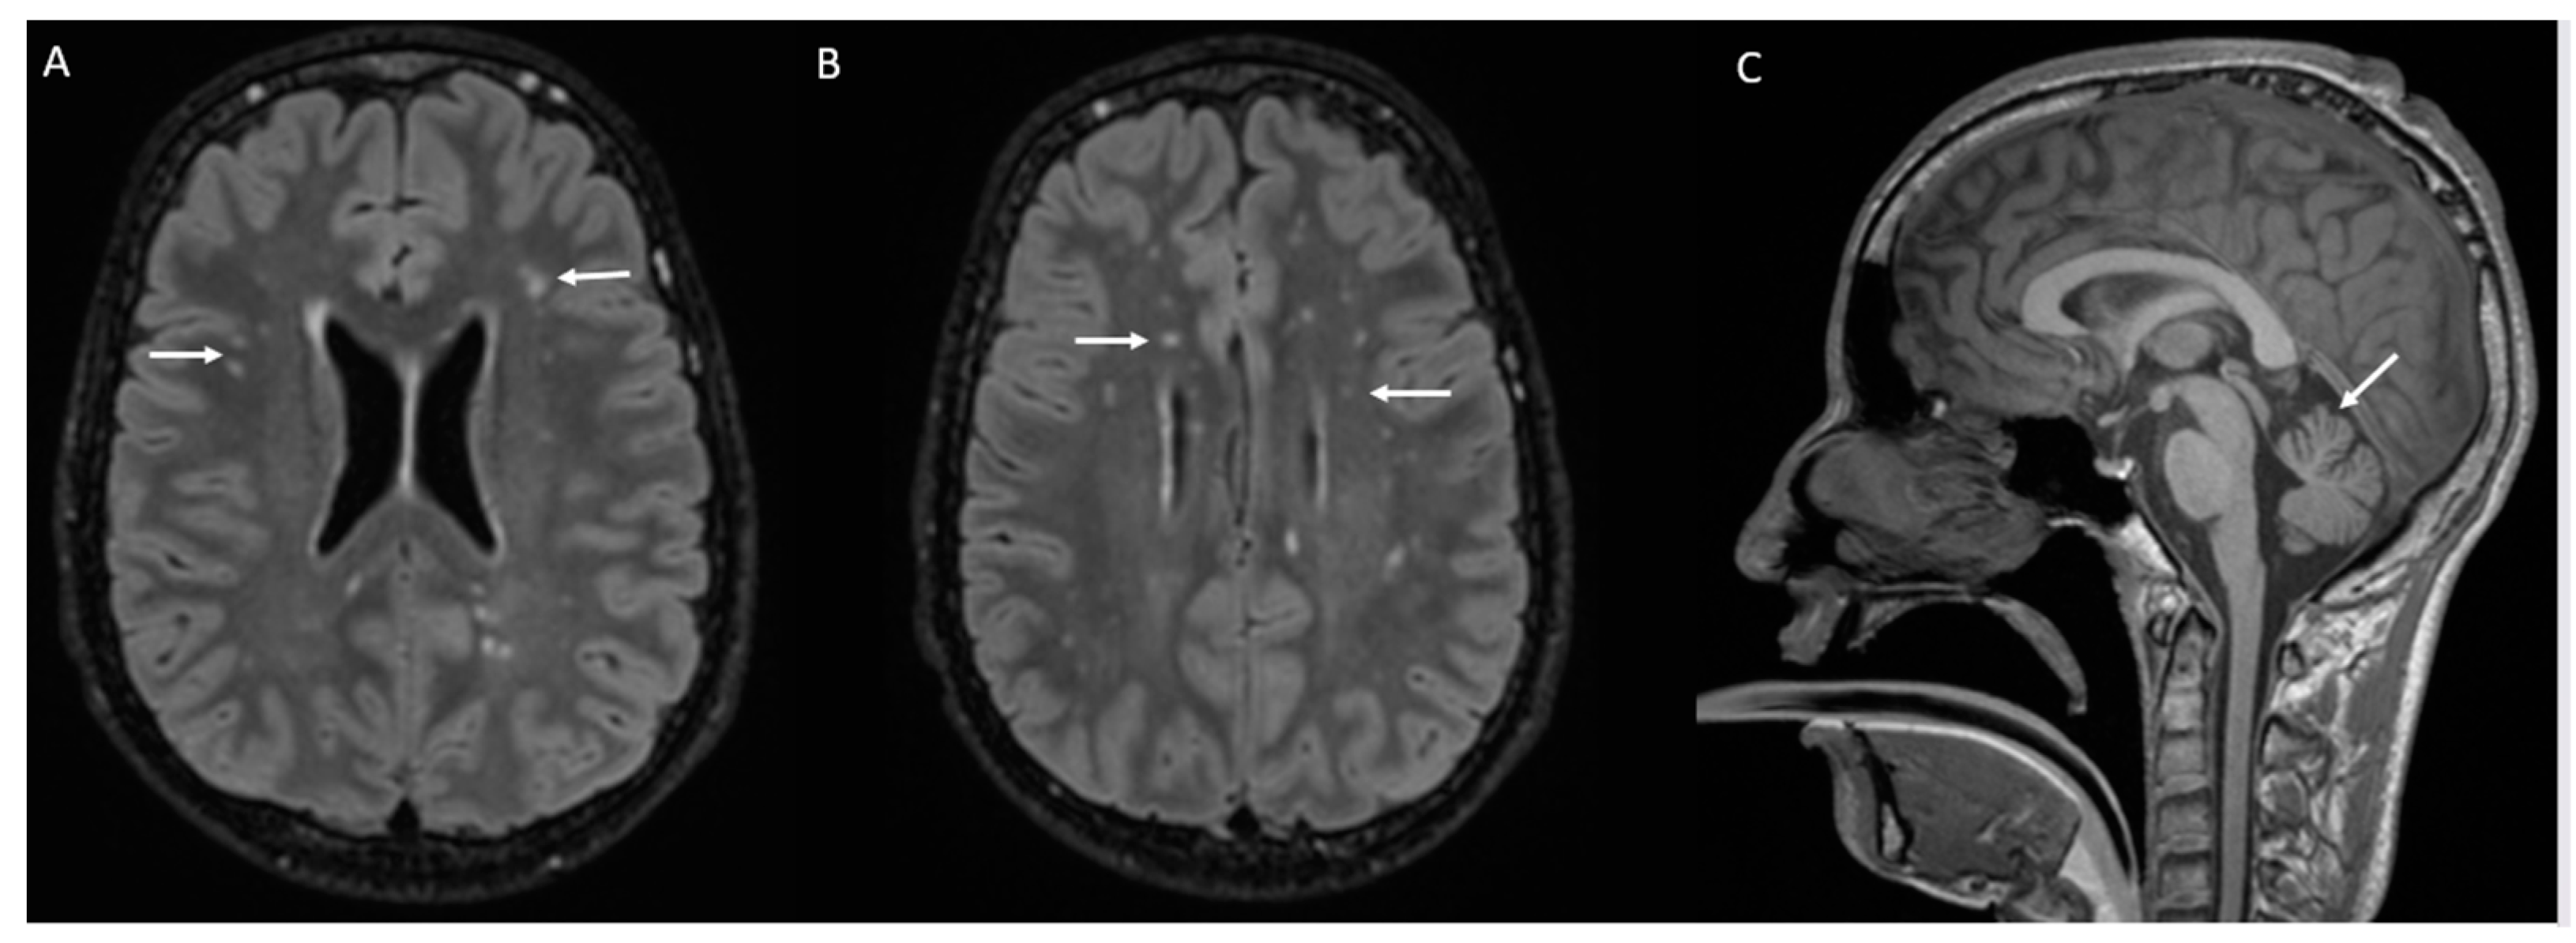

| Brain MRI: | |||||

| Cerebellar atrophy | + | + | + | + | |

| Multiple periventricular FLAIR signals | + | + | - | - | |